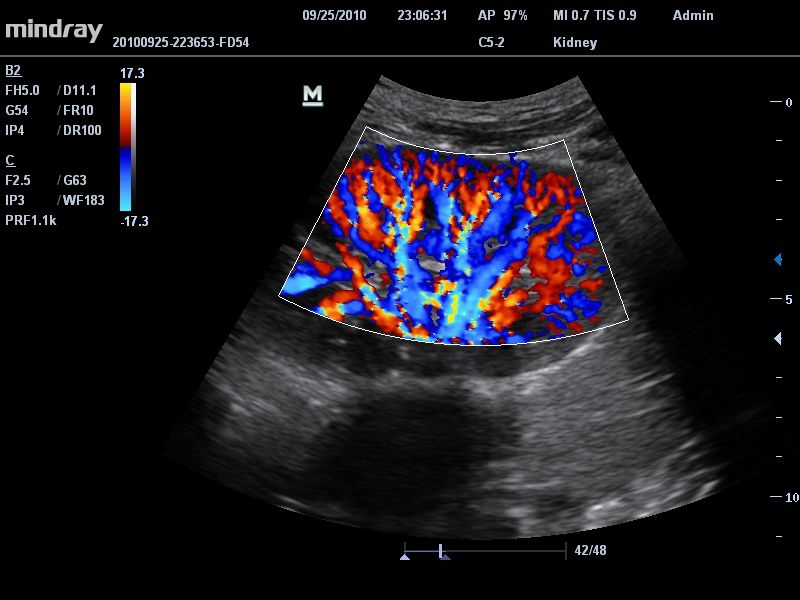

Цветовой допплер:

Да

• Режимы сканирования: B/M/CFM/PDI/Направленный PDI/PW, HPRF, Тканевая гармоника, М- и цветной М-режим.

• IMT: автоматический расчет толщины интима-медиа сосудов.